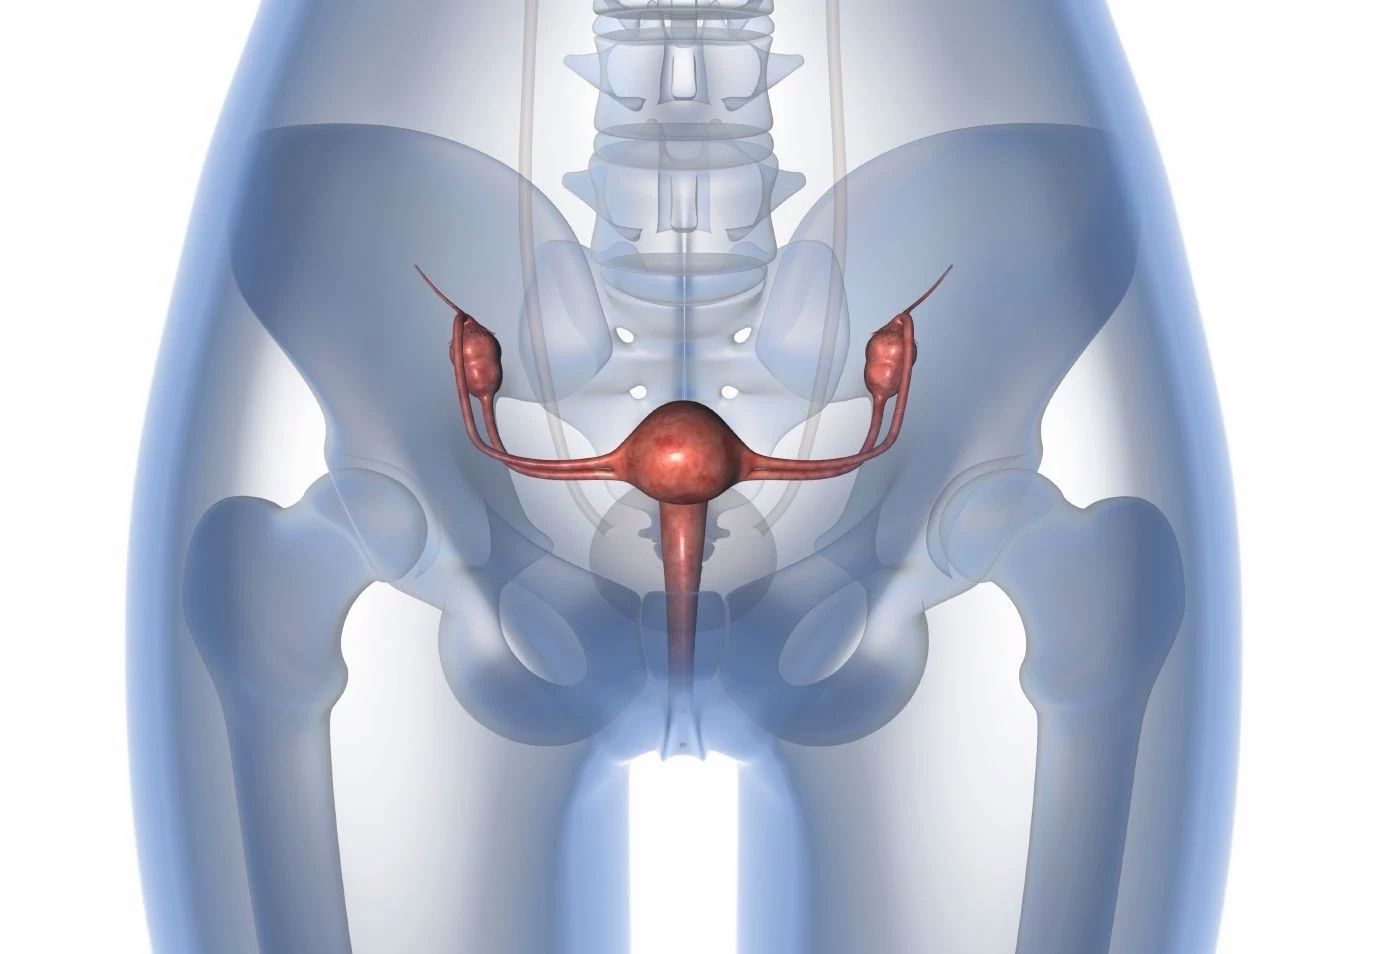

Анатомия малого таза: детальные схемы и изображения